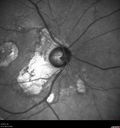

Macular Telangiectasis and Vision loss following vitrectomy with membrane peel451 views76 year old man with MacTel who had membrane peel in the right eye 10 years ago with permanent vision loss.

VA OD: sc20/200-4 and VA OS: sc20/25-1